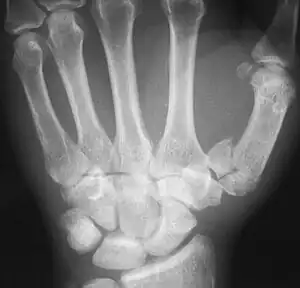

| Rolando fracture - a comminuted intra-articular fracture of the first metacarpal bone. | |

The cause is generally a force along the long axis of the thumb, such as during a fight.[3][4] Diagnosis is by medical imaging; such as X-ray, CT scan, or MRI.[3] It results in at least three bone fragments, which often form a T- or Y-shaped pattern.[3][4] It differs from a Bennett fracture which only results in two bone fragments.[4]

'Y-shaped' Rolanda fracture